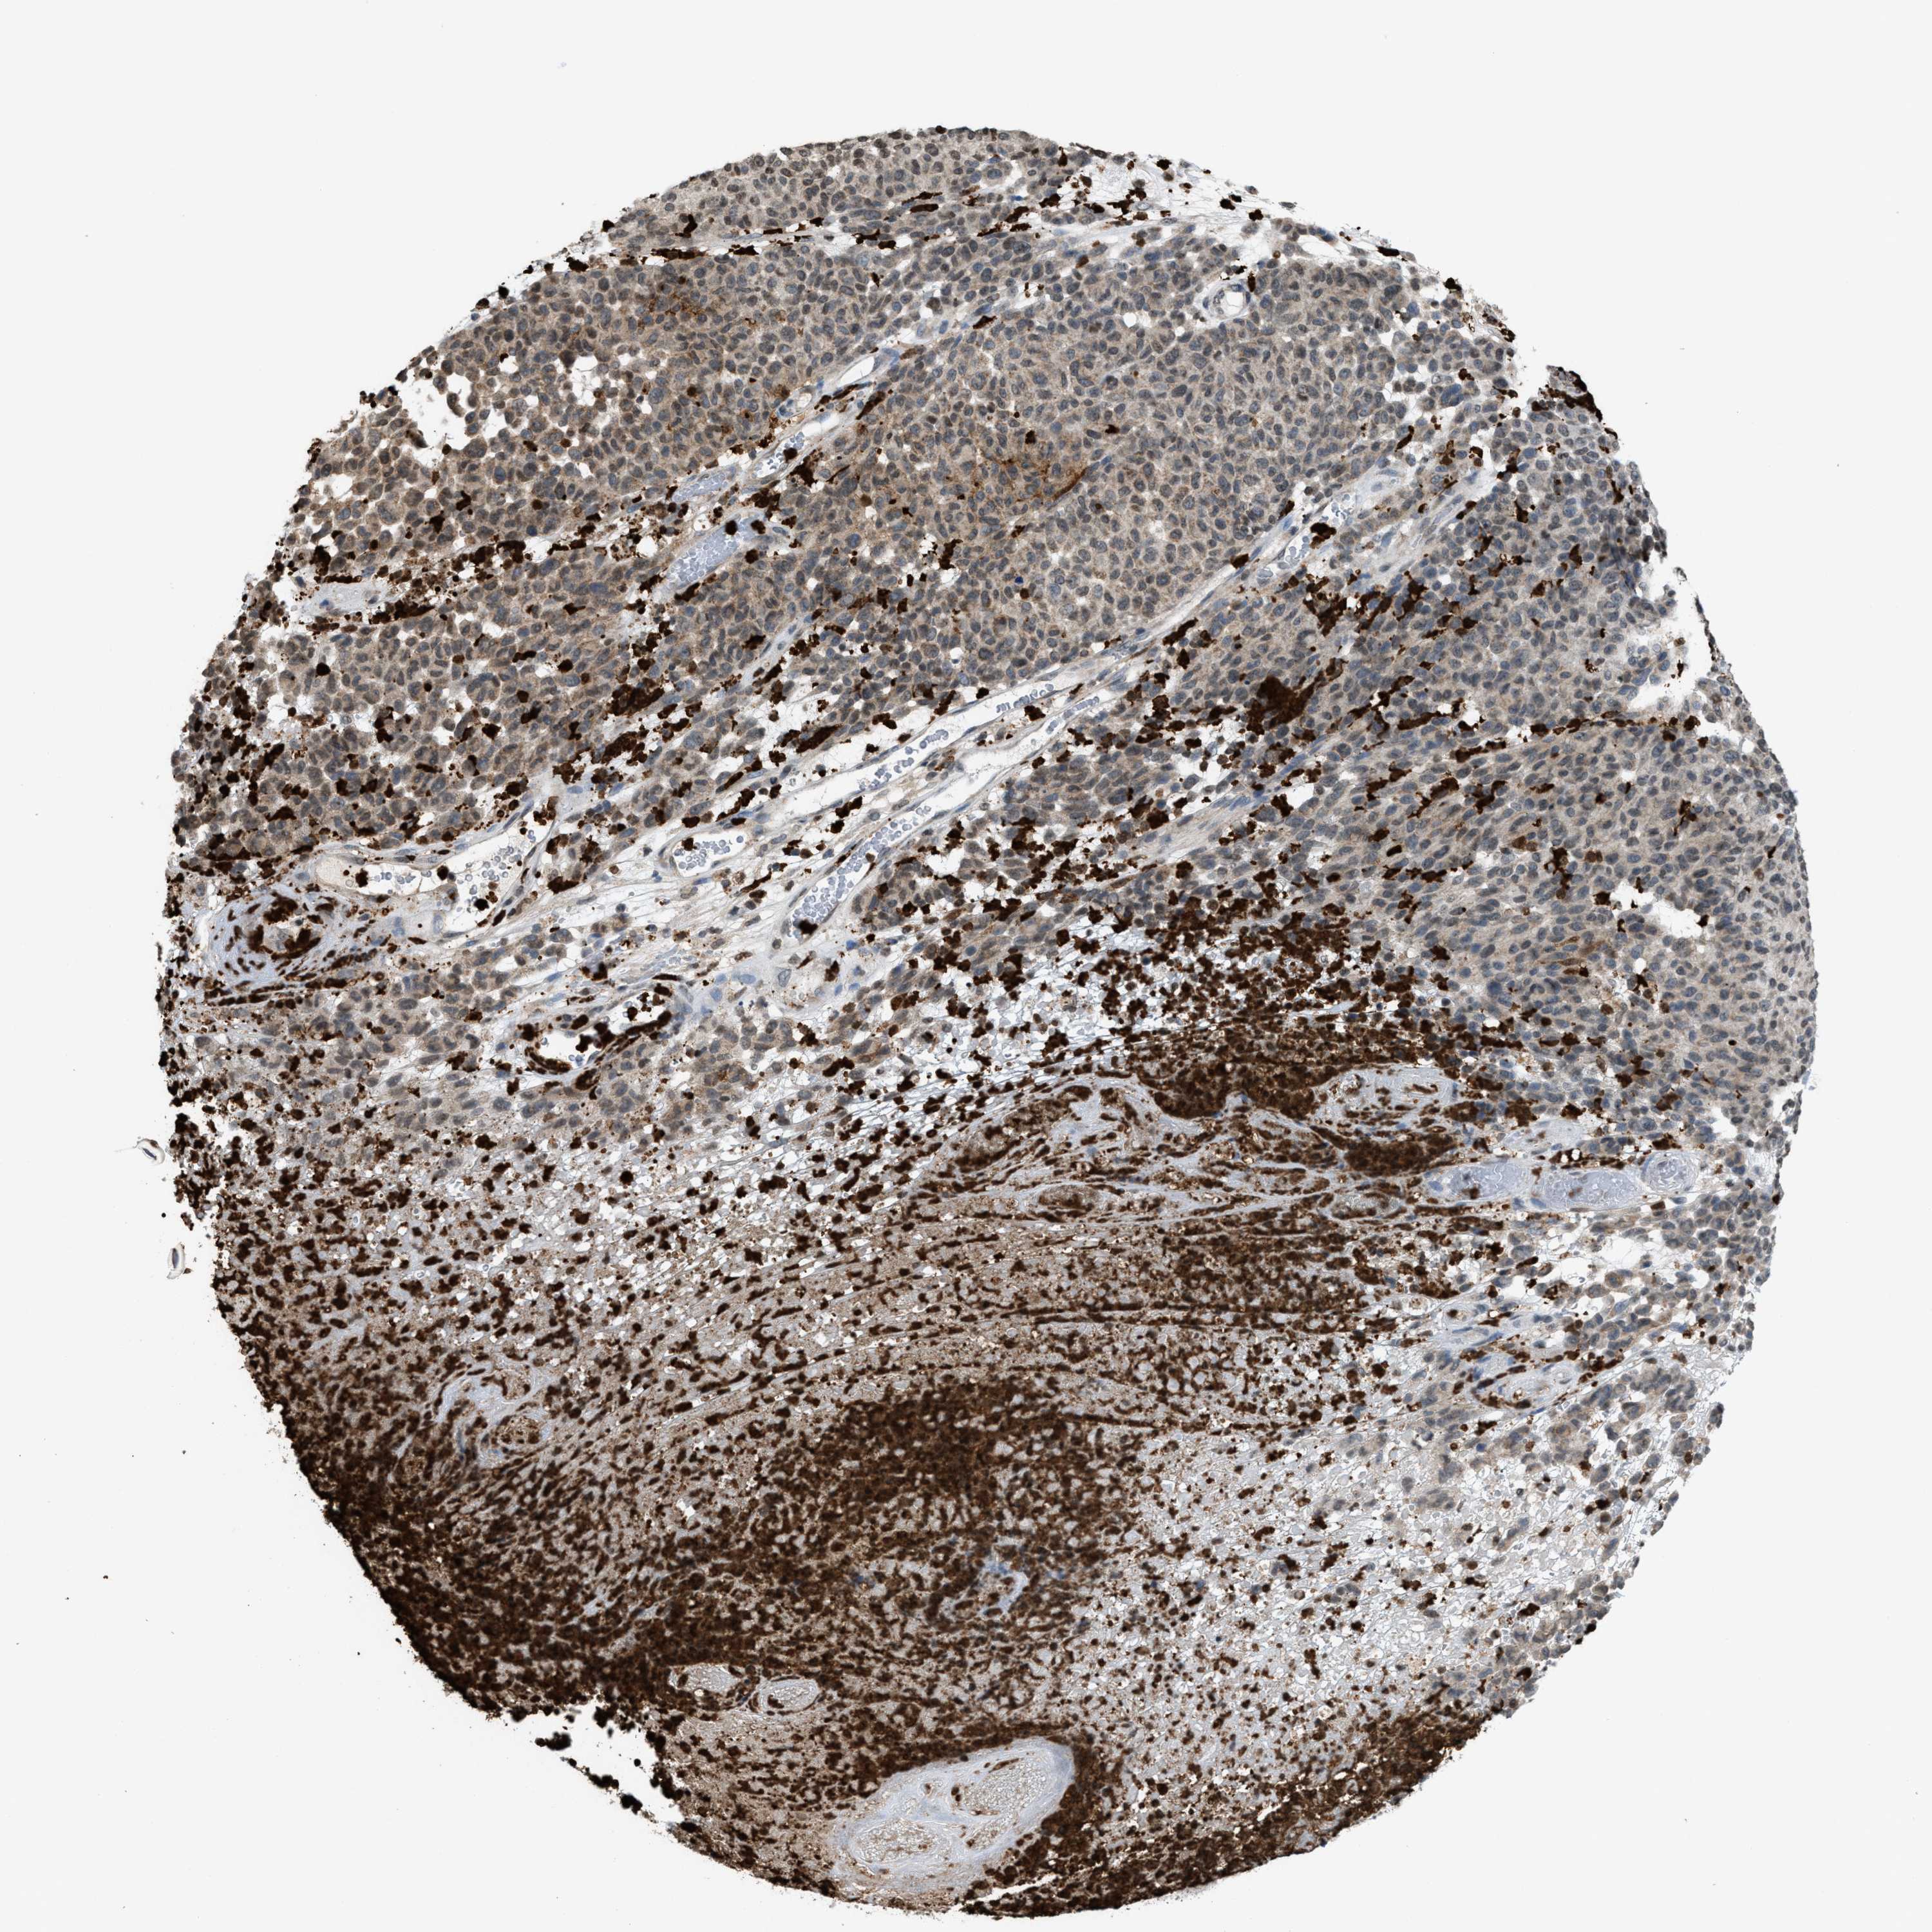

MELANOMA - Protein expressioni

A mouse-over function shows sample information and annotation data. Click on an image to view it in a full screen mode. Samples can be filtered based on level of antibody staining by selecting one or several of the following categories: high, medium, low and not detected. The assay and annotation is described here.

Note that samples used for immunohistochemistry by the Human Protein Atlas do not correspond to samples in the TCGA dataset.

Antibody stainingi

Antibody staining in the annotated cell types in the current human tissue is reported as not detected, low, medium, or high, based on conventional immunohistochemistry profiling in selected tissues. This score is based on the combination of the staining intensity and fraction of stained cells.

Each image is clickable and will lead to virtual microscopy that enables deeper exploration of all samples and also displays staining intensity scores, fraction scores and subcellular localization as well as patient and tissue information for each sample.

Antibody HPA022470

Antibody HPA031079

Staining

High

Medium

Low

Not detected

Intensity

Strong

Moderate

Weak

Negative

Quantity

>75%

75%-25%

<25%

None

Location

Nuclear

Cytoplasmic/membranous

Cytoplasmic/membranous,nuclear

Malignant melanoma, NOS

Malignant melanoma, Metastatic site